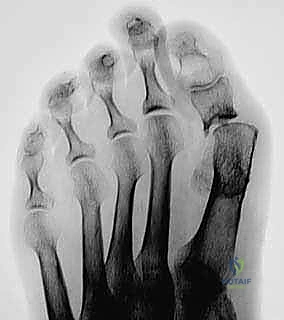

- Most commonly, the severe ankle and hindfoot deformity with talar fragmentation and resorption is seen in diabetic neuropathy. Other causes of Charcot arthropathy include tabes dorsalis, Hansen disease, syringomyelia, alcoholic neuropathy, Charcot-Marie-Tooth disease, lumbar radiculopathy, peripheral nerve lesions, Riley-Day syndrome, renal dialysis, congenital insensitivity to pain, and intra-articular steroid injections. Similar changes on radiographs can be seen in inflammatory arthritis, and in posttraumatic arthritis with talar avascular necrosis ( FIG 2 ).

FIG 1 • A. Unbraceable Charcot ankle and hindfoot deformity, even with a Charcot retention orthotic walker (CROW). B. Lateral radiograph of Charcot neuroarthropathy of the ankle.

The diabetic with peripheral neuropathy typically has dry, flaky, hairless skin distally. The extremity may exhibit swelling, redness, and warmth. Patients complain of dysesthesia (eg, stinging, burning, cramping) rather than anesthesia. Stage 0 patients may complain of sprain-type pain and deep joint or deep bone pain, with or without a clear history of injury. Early, there may be little if any swelling. Later, as stage I approaches, swelling occurs. As the peripheral motor neuropathy progresses, Achilles contracture occurs. The appearance of a high arch in the foot actually may represent intrinsic muscle wasting. Early on before collapse occurs, the foot appearance is similar to that seen in Charcot-Marie-Tooth disease. Pulses in the extremity are usually present ( FIG 4 ).